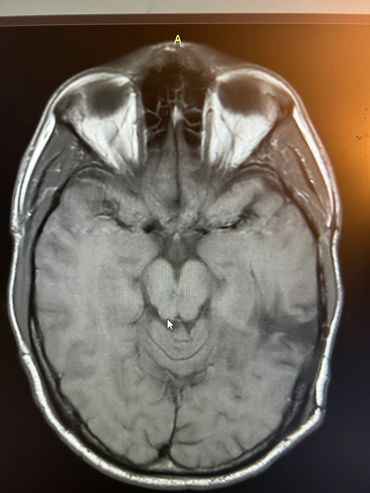

Axial MRI scan showing detailed brain structures including eye sockets and brain tissue.